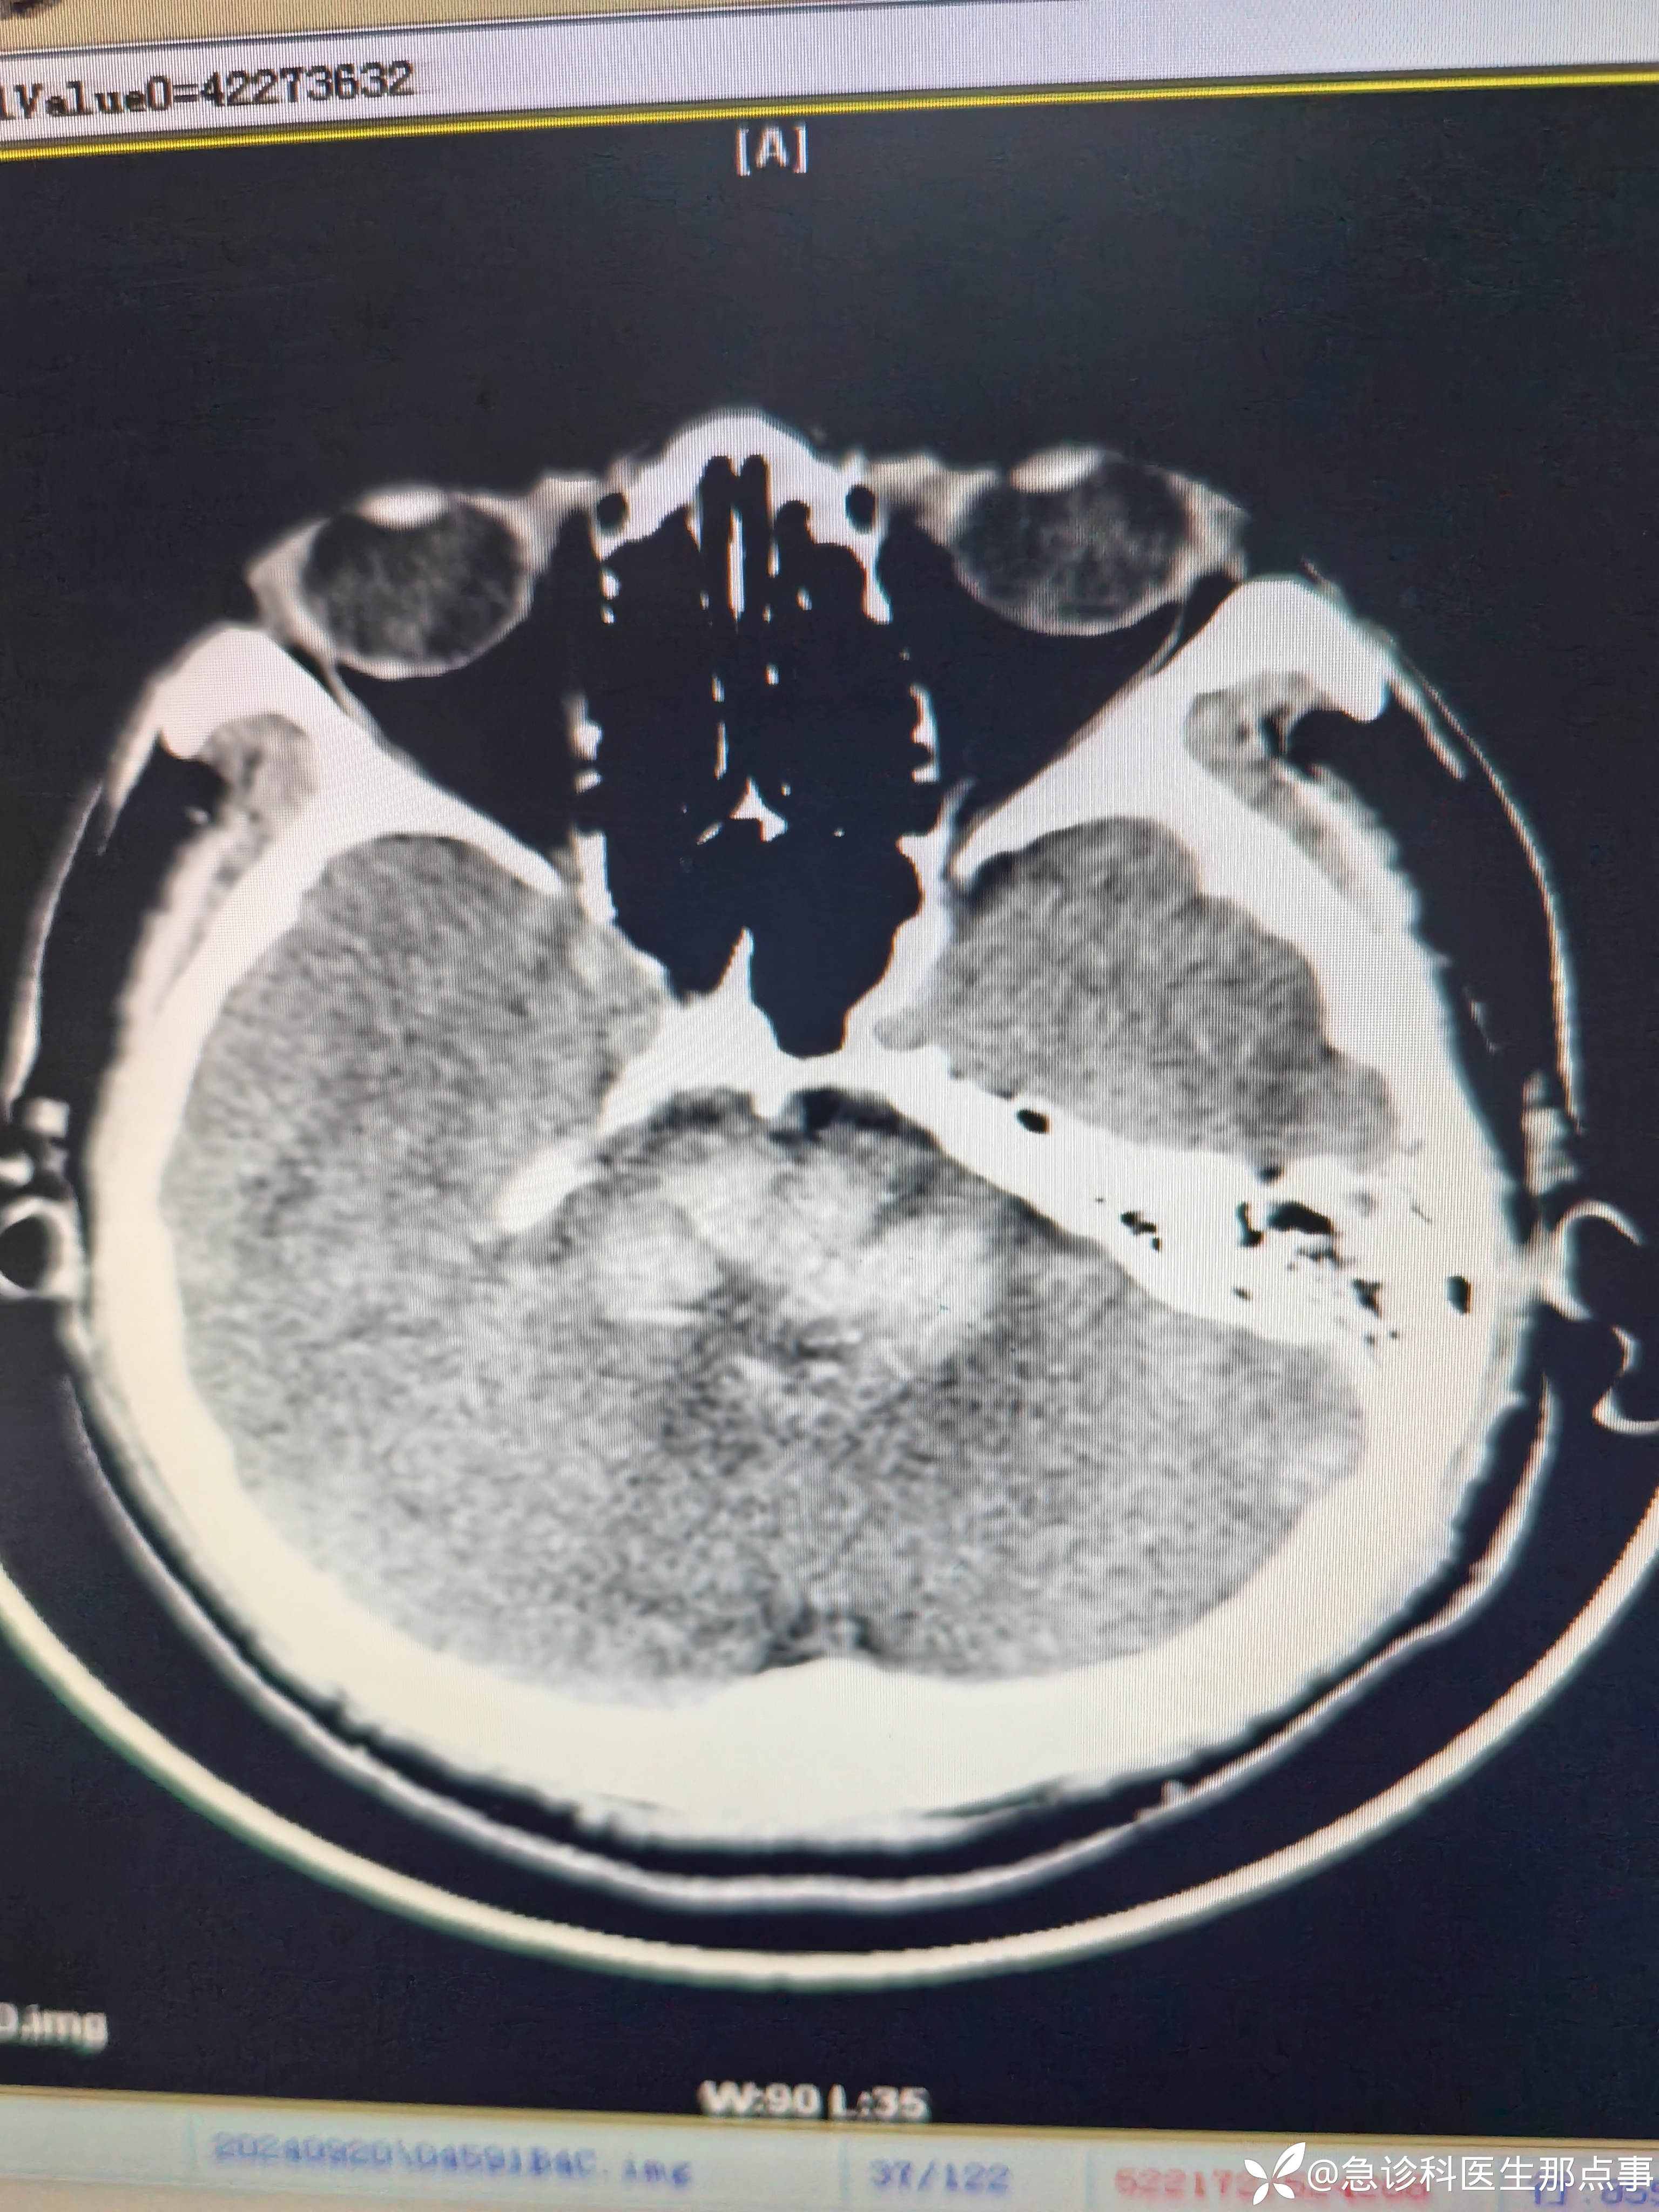

【患者信息】:男,40岁

【主诉】:突发意识不清伴双下肢间歇性痉挛抽搐半小时。

【现病史及既往史】:高血压病,间断口服药物。

【检查】:血压235/114心率82指脉氧99%意识不清,口吐白沫,双下肢间歇性痉挛抽搐。

【临床诊断】:脑干出血

【治疗经过及结果】:监护,吸氧,甘露醇快速静滴。